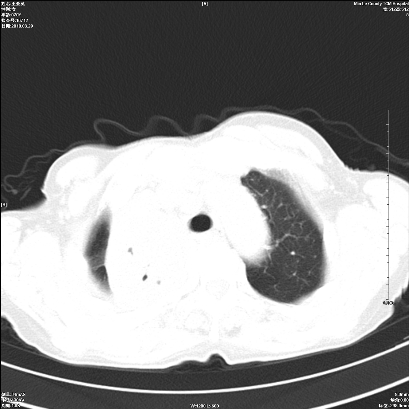

标题: CT25424:女性,70岁,胸闷、咳嗽月余。 [打印本页]

标题: CT25424:女性,70岁,胸闷、咳嗽月余。

右肺上叶支气管开口阻塞,上叶呈不均匀致密影,右肺中下叶内见斑片状密度增高影,上叶见钙化点,纵隔内见钙化淋巴结,桶状胸,右下肺动脉增粗,残根征,意见:1.右肺中心性肺癌;2.右肺陈旧性结核;3.肺心病。

ct所见:右肺上叶肺不张,呈软组织密度影向肺门区聚拢,其内可见含气段支气管及细支气管影,病灶内尚可见钙化结节。右肺上叶支气管狭窄,段支气管壁可见钙化。右肺下叶背段、右肺中叶见不规则小片絮状影及纤维条索影,形态较僵硬。右肺中叶胸膜旁可见多个小结节影。纵膈内见钙化淋巴结。

分析:右侧胸廓及右肺体积缩小,说明病变时间比较长了,应该是有数年的时间了,如果是短期内出现的肺不张,只会引起纵膈向患侧移位,而不会引起胸廓的塌陷。不张的肺组织内可见含气支气管影,说明右肺上叶支气管没有完全中断,只是狭窄。右肺中叶、下叶散在不规则病灶,部分呈纤维化改变。纵膈内的淋巴结大部分钙化。因此,本例给我的感觉良性病变的可能是大。

结论:考虑右肺上叶支气管内膜结核合并右肺上叶肺不张;右肺中叶、下叶陈旧性肺结核改变。